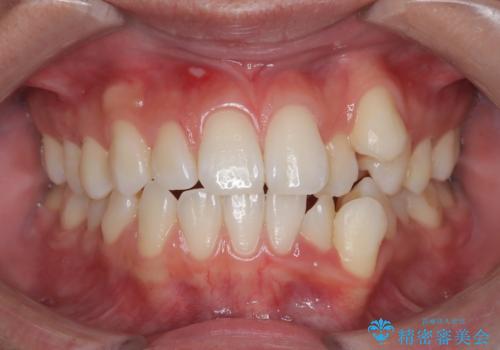

【審美装置】前歯のがたがたを治したい

- 前歯の凸凹と口元の突出感を主訴に来院されました。

臼歯関係が上顎前突傾向のため、上の小臼歯を抜歯してワイヤー矯正を行なっております。

下顎の叢生はIPRを行なって配列しています。